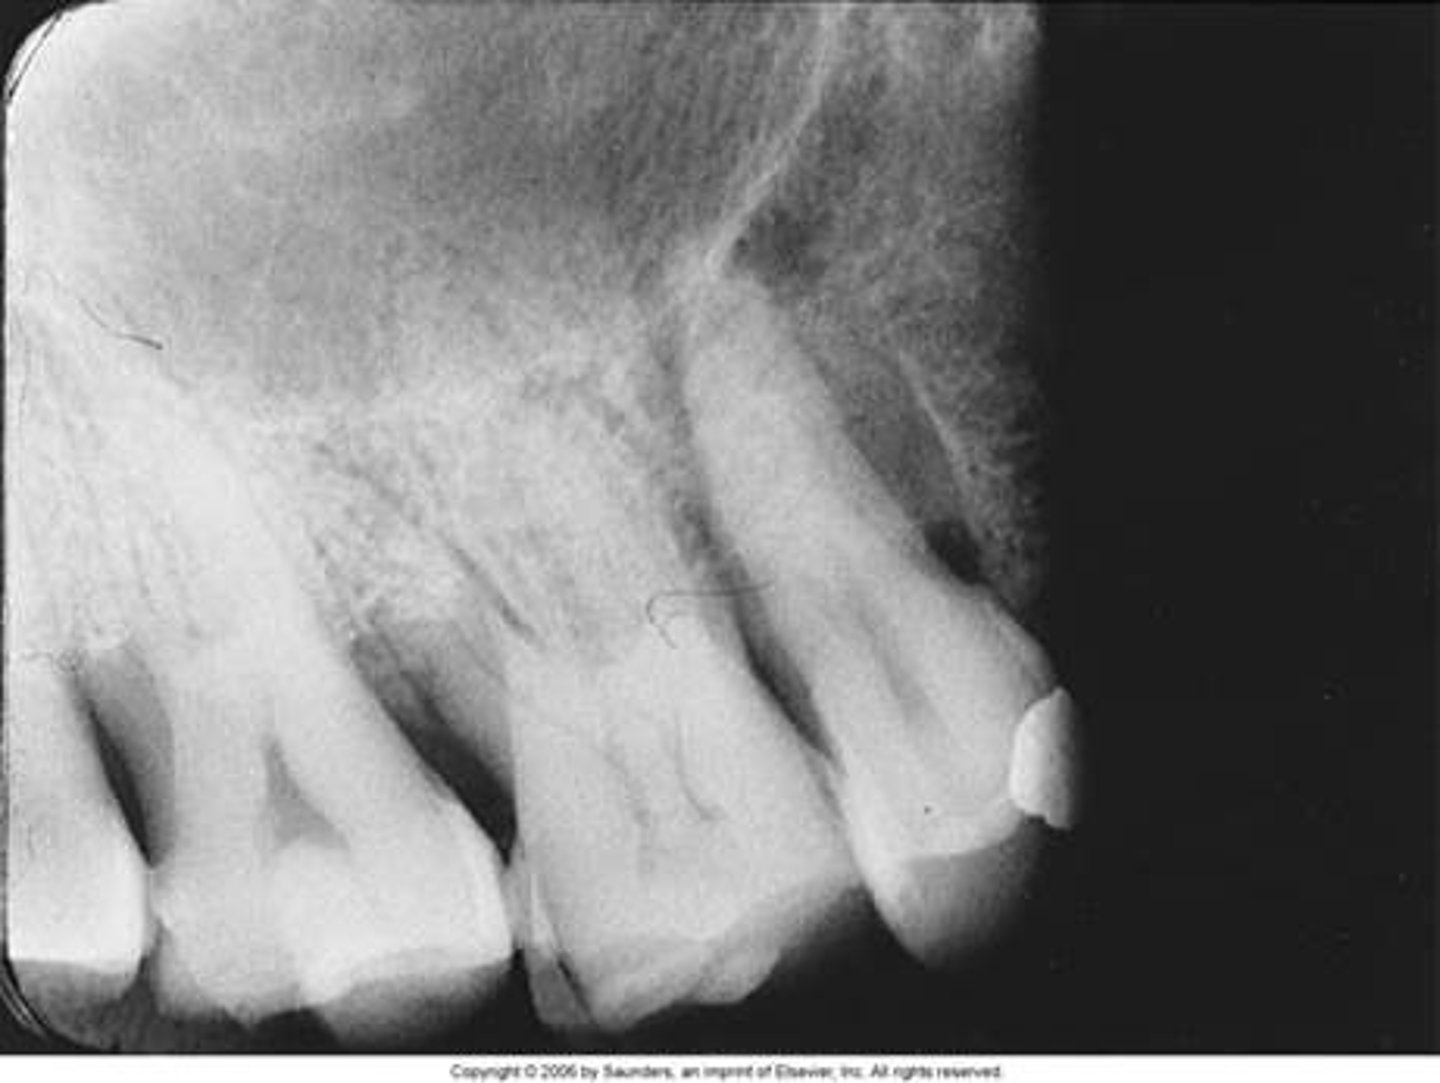

Phalangioma

Distal phalanx of the finger is seen in the radiograph

<p>Distal phalanx of the finger is seen in the radiograph</p>